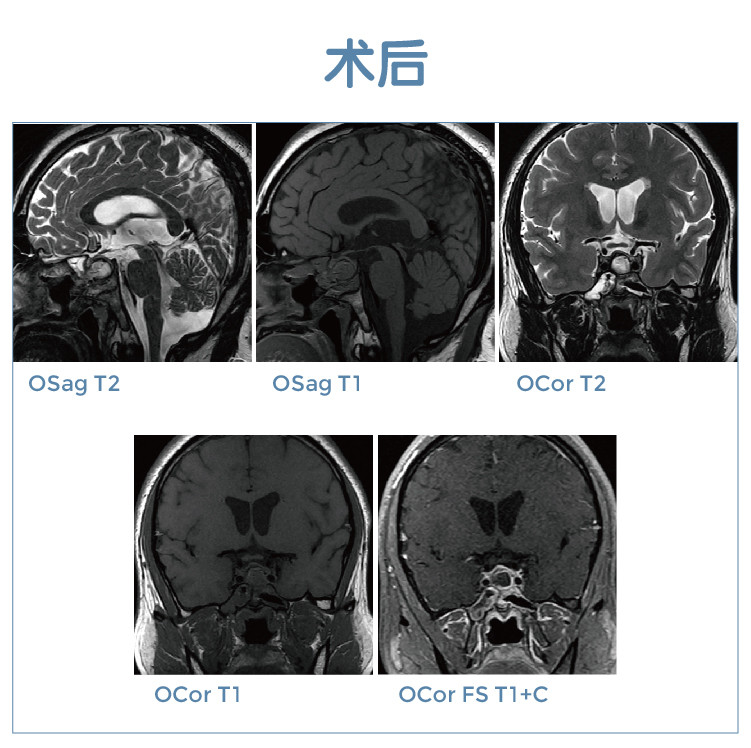

【朗润影像档案】20191122磁共振影像病例结果讨论